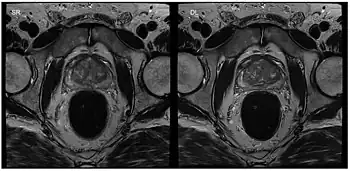

Apart from cardiac MRI other real-time applications deal with functional studies of joint kinetics (e.g., temporomandibular joint,[29] knee and the wrist[30]) or address the coordinated dynamics of the articulators such as lips, tongue, soft palate and vocal folds during speaking (articulatory phonetics)[31] or swallowing.[32] Musculoskeletal imaging in particular benefits from real-time observation. Researchers at the NYU Grossman School of Medicine[33] developed a RT-MRI glove for imaging movement of the hand. The glove uses high impedance coils to prevent the generation of eddy currents from rapidly changing magnetic fields and bSSFP for rapid imaging times. High-impedance coils remove the need for specific coil conformations and active gradient shielding.[34]